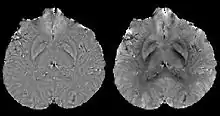

Morphology enabled dipole inversion (MEDI)

A unique advantage of MRI is that it provides not only the phase image but also the magnitude image. In principle, the contrast change, or equivalently the edge, on a magnitude image arises from the underlying change of tissue type, which is the same cause for the change of susceptibility. This observation is translated into mathematics in MEDI,[13] where edges in a QSM which do not exist in the corresponding magnitude image are sparsified by solving a weighted norm minimization problem.[14]

MEDI has also been validated extensively in phantom, in vitro and ex vivo experiments. In an in vivo human brain, MEDI calculated QSM showed similar results compared to COSMOS without statistically significant difference.[15] MEDI only requires a single angle acquisition, so it is a more practical solution to QSM.